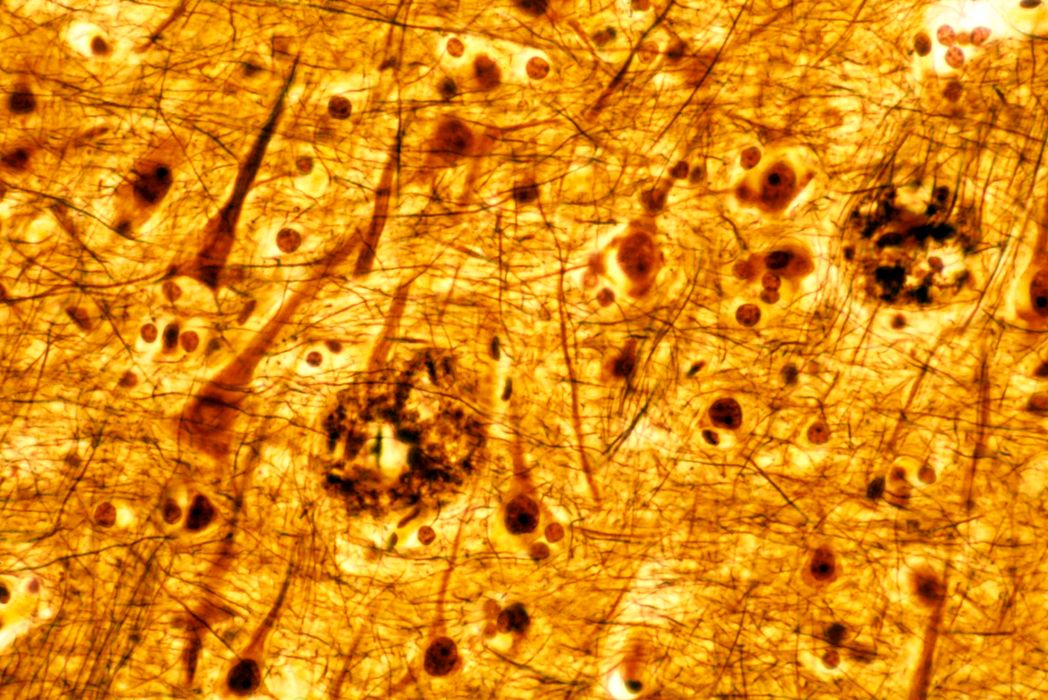

Cancerul ar putea emite semnale care protejează creierul împotriva bolii Alzheimer

Cancerul și boala Alzheimer sunt două dintre cele mai temute diagnostice din medicină, însă ele apar rareori la aceeași persoană. Asta deoarece cancerul ar putea emite semnale care protejează creierul împotriva bolii Alzheimer, spun cercetătorii. […]